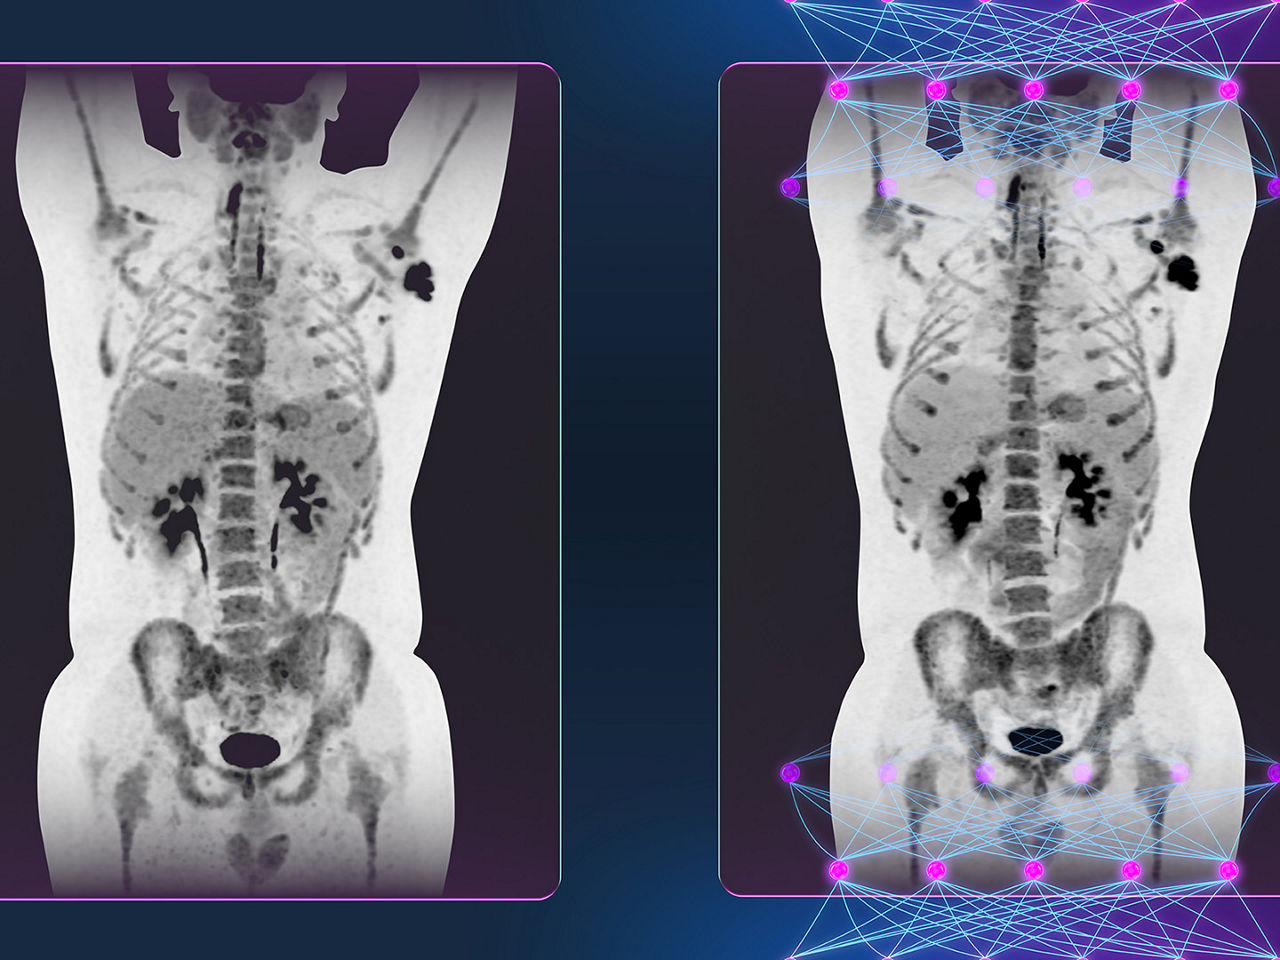

The new PET/CT platform was built to exceed industry sensitivity standards, creating the potential to image high count rate tracers beyond 18F-fluorodeoxyglucose (FDG) as they are developed and utilized in clinical PET/CT imaging. TOF image quality performance benefits in the new system are made possible with an innovative deep-learning solution designed to increased small, low-contrast lesion detectability compared to Time-of-Flight systems.**

Unique in molecular imaging, the system’s deep learning image processing is achieved using a CNN, trained on thousands of PET/CT images constructed via various reconstruction methods, including TOF. The CNN learns the characteristics of each image; therefore, the resulting images provide image quality performance benefits most associated with hardware-based TOF systems, such as better contrast-to-noise ratio and contrast recovery.w Deep learning techniques using CNNs enhance images with the image quality performance benefits most associated with TOF without investing in more hardware or new equipment.